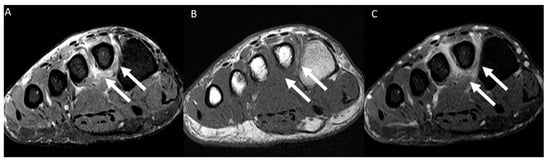

| Muscular edema | 112/130 (86.2%) | 70/86 (81.4%) | 42/44 (95.5%) | p = 0.028 |

| Intravascular signal characteristics on T2-weighted images | High 108/130 (83.1%) | High 68/86 (79.1%) | High 40/44 (90.9%) | p = 0.044 |

| Perivascular edema | 130/130 (100%) | 86/86 (100%) | 44/44 (100%) | p > 0.999 |

| Perivascular enhancement | 130/130 (100%) | 86/86 (100%) | 44/44 (100%) | p > 0.999 |

| Intravenous filling defect | 127/130 (97.7%) | 84/86 (97.7%) | 43/44 (97.7%) | p > 0.999 |

| Venous ectasia | 130/130 (100%) | 86/86 (100%) | 44/44 (100%) | p > 0.999 |